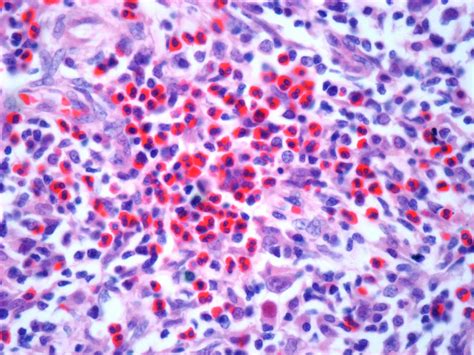

• Biopsy: This is the definitive test. A small sample of a lymph node or affected tissue is removed and examined under a microscope.

• lymphoma itchy skin pictures